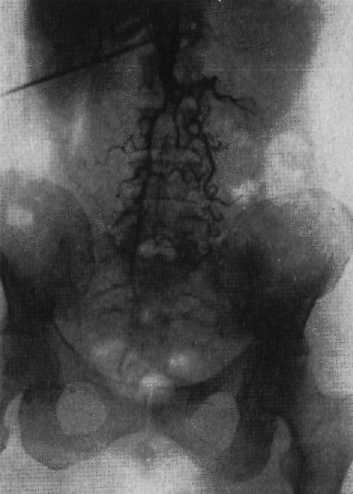

1) Назовите рентгеноконтрастный метод исследования сосудов. Какова его диагностическая ценность при облитерирующих заболеваниях сосудов?

2) Укажите на аортограмме признаки окклюзии аорты.

1) Ангиография – рентгенологическое исследование артерий и вен после введения в них контрастного вещества. Ангиография при облитерирующих заболеваниях сосудов позволяет определить сужение сосуда вплоть до его непроходимости.

2) На аортограмме видно, что контрастное вещество заполнило лишь проксимальную часть брюшной аорты, эта часть деформирована и сужена. Дальнейшее продвижение контрастного вещества по брюшной аорте оказалось невозможным из-за ее полной окклюзии, вследствие поражения атеросклерозом.